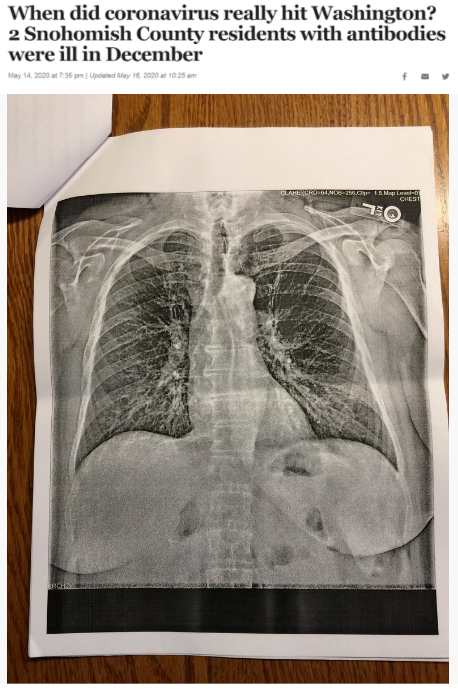

據(jù)《西雅圖時(shí)報(bào)》去年5月14日報(bào)道,華盛頓州斯諾霍米什縣的兩位居民在2019年12月出現(xiàn)類似新冠肺炎的癥狀,之后對他們的新冠病毒抗體檢測呈陽性反應(yīng)。這一結(jié)果表明,新冠病毒可能比想象中更早在當(dāng)?shù)爻霈F(xiàn)。

△《西雅圖時(shí)報(bào)》報(bào)道截圖(題圖中的X光片顯示其中一位斯諾霍米什縣居民的肺部“過度充氣”并出現(xiàn)“線性混濁”。醫(yī)生認(rèn)為,這可能是疊加上呼吸道肺部感染的表現(xiàn)。)